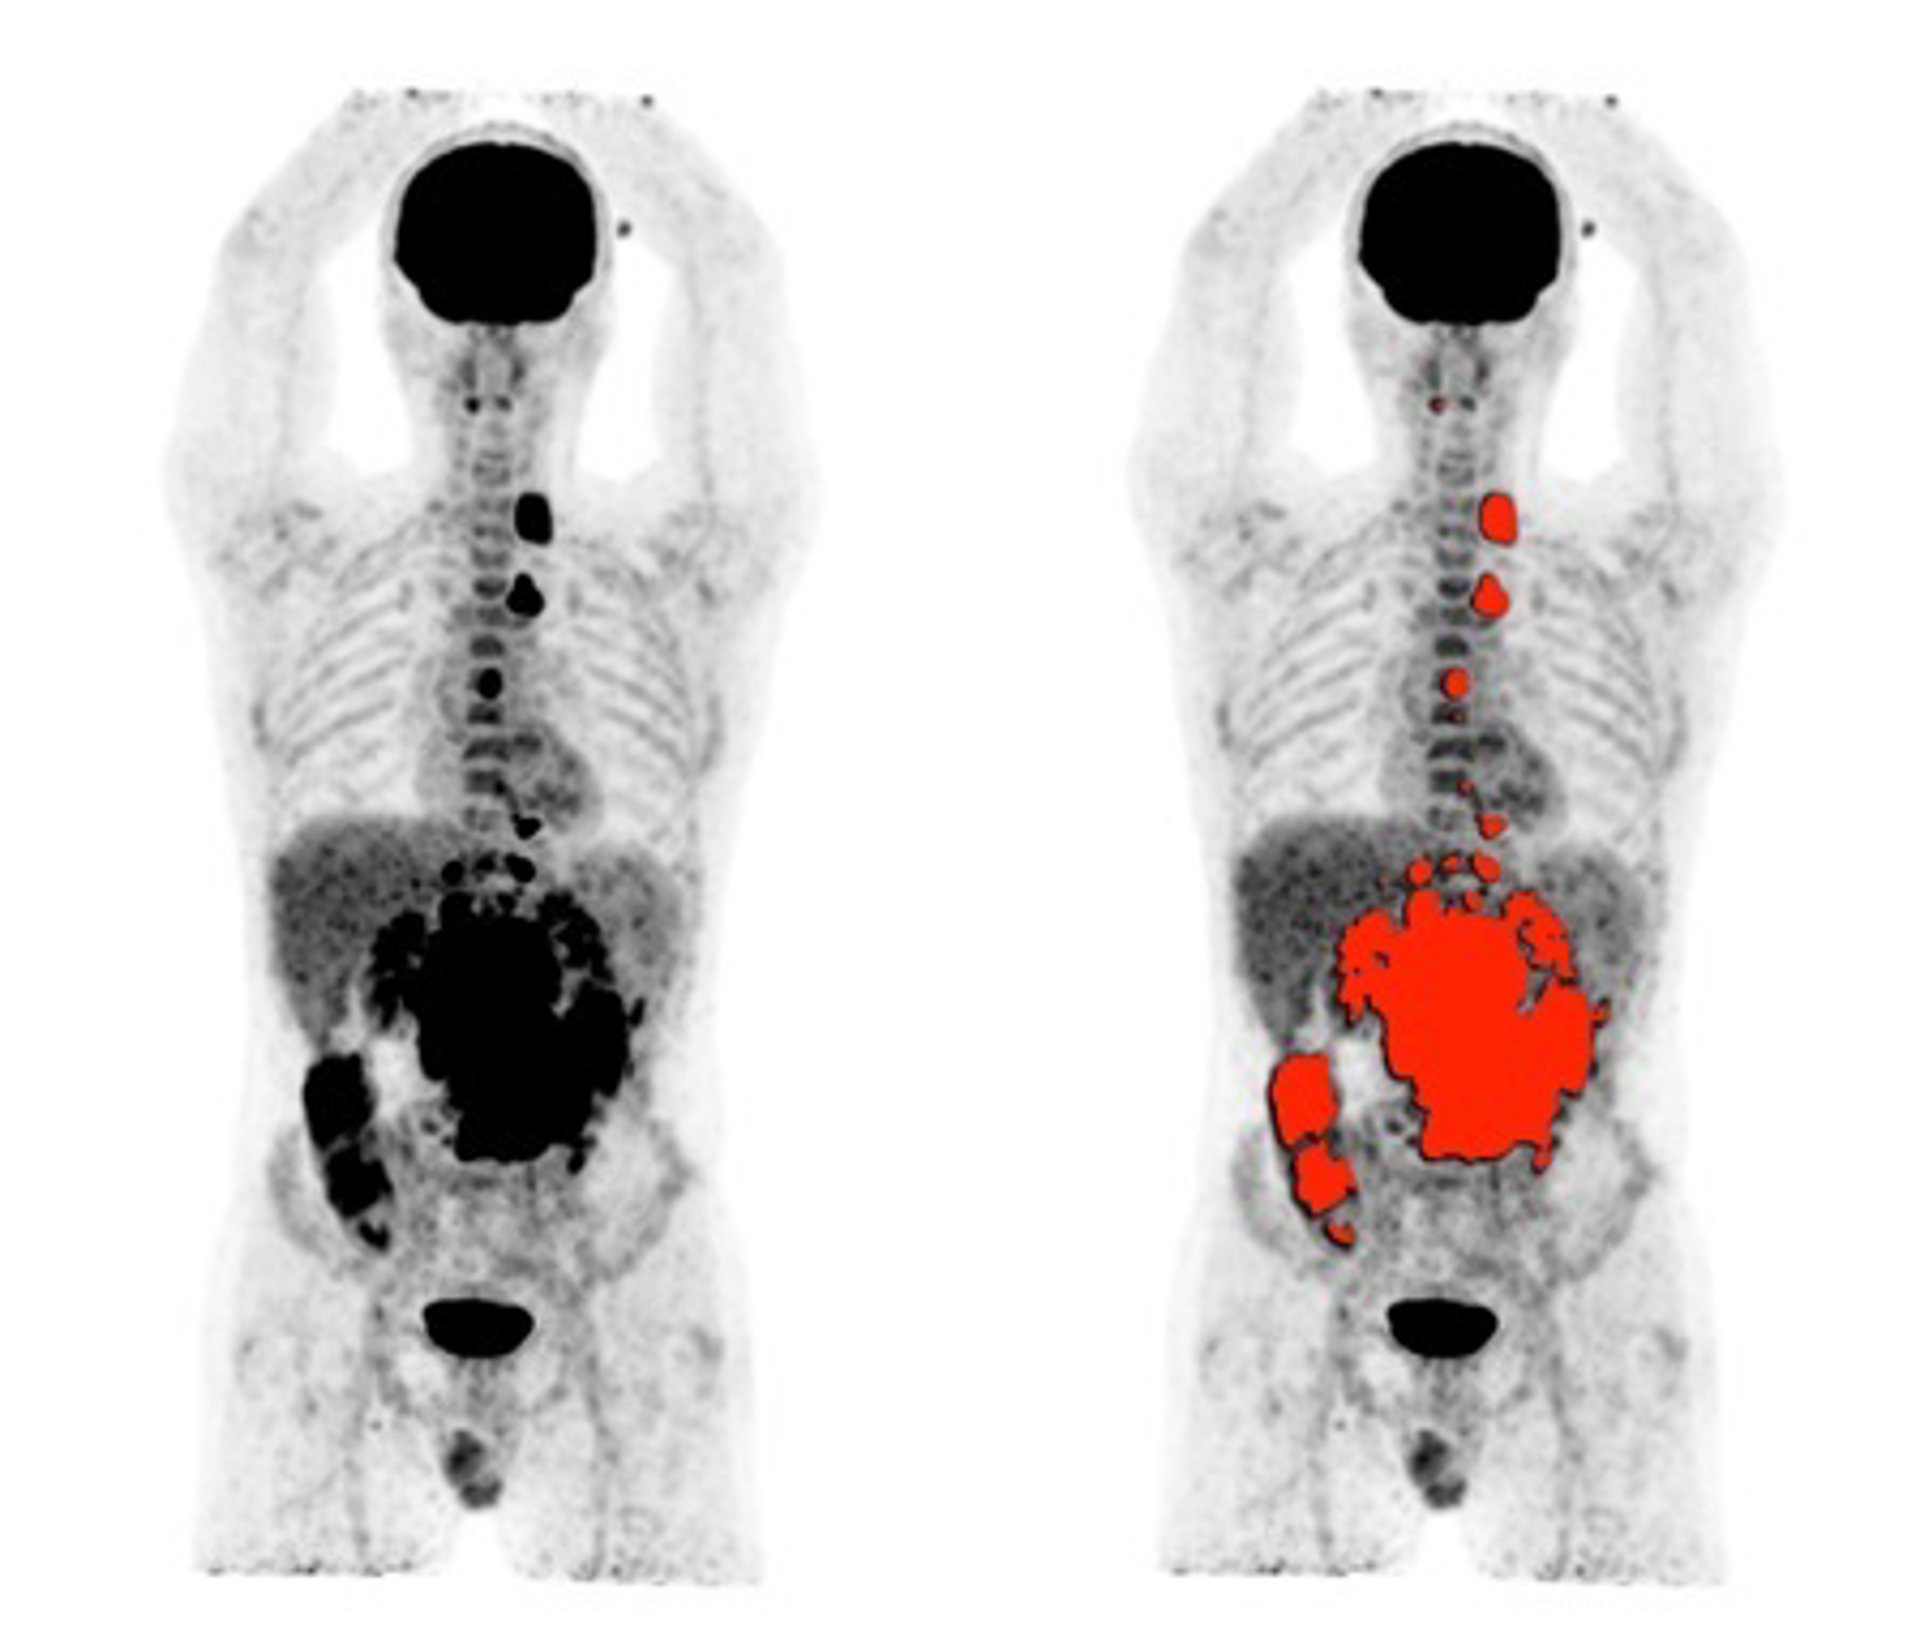

Un proyecto del Consejo Superior de Investigaciones Científicas (CSIC), la Universitat Politcnica de Valncia (UPV) y la Universitat de Valncia (UV) busca desarrollar un nuevo dispositivo de tomografía por emisión de positrones (PET) que mejore las prestaciones de los equipos actuales, gracias al aumento de la sensibilidad y resolución espacial.

Además, según informan, este nuevo desarrollo permite aumentar de manera significativa su extensión axial y abarcar el cuerpo completo del paciente. Además, la tecnología podrá reducir más aún la dosis de radiación asociada a este equipo, lo que tendrá un efecto beneficioso directo en los casos de seguimiento de respuesta a tratamientos en los que son necesarios realizar varios estudios PET.

Los dispositivos PET se centran en la obtención de imágenes moleculares, que utilizan radiofármacos específicos para generar la imagen funcional de un órgano o proceso metabólico en particular. La imagen molecular mediante PET está ayudando en todas las etapas del estudio oncológico del paciente, tanto en el diagnóstico inicial como en el seguimiento, guía para biopsia o planificación de quimio/radioterapia.